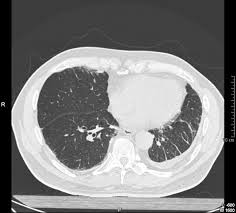

Pleural Plaques From Asbestos British Lung Foundation

Pleural Plaques From Asbestos British Lung Foundation from www.blf.org.uk